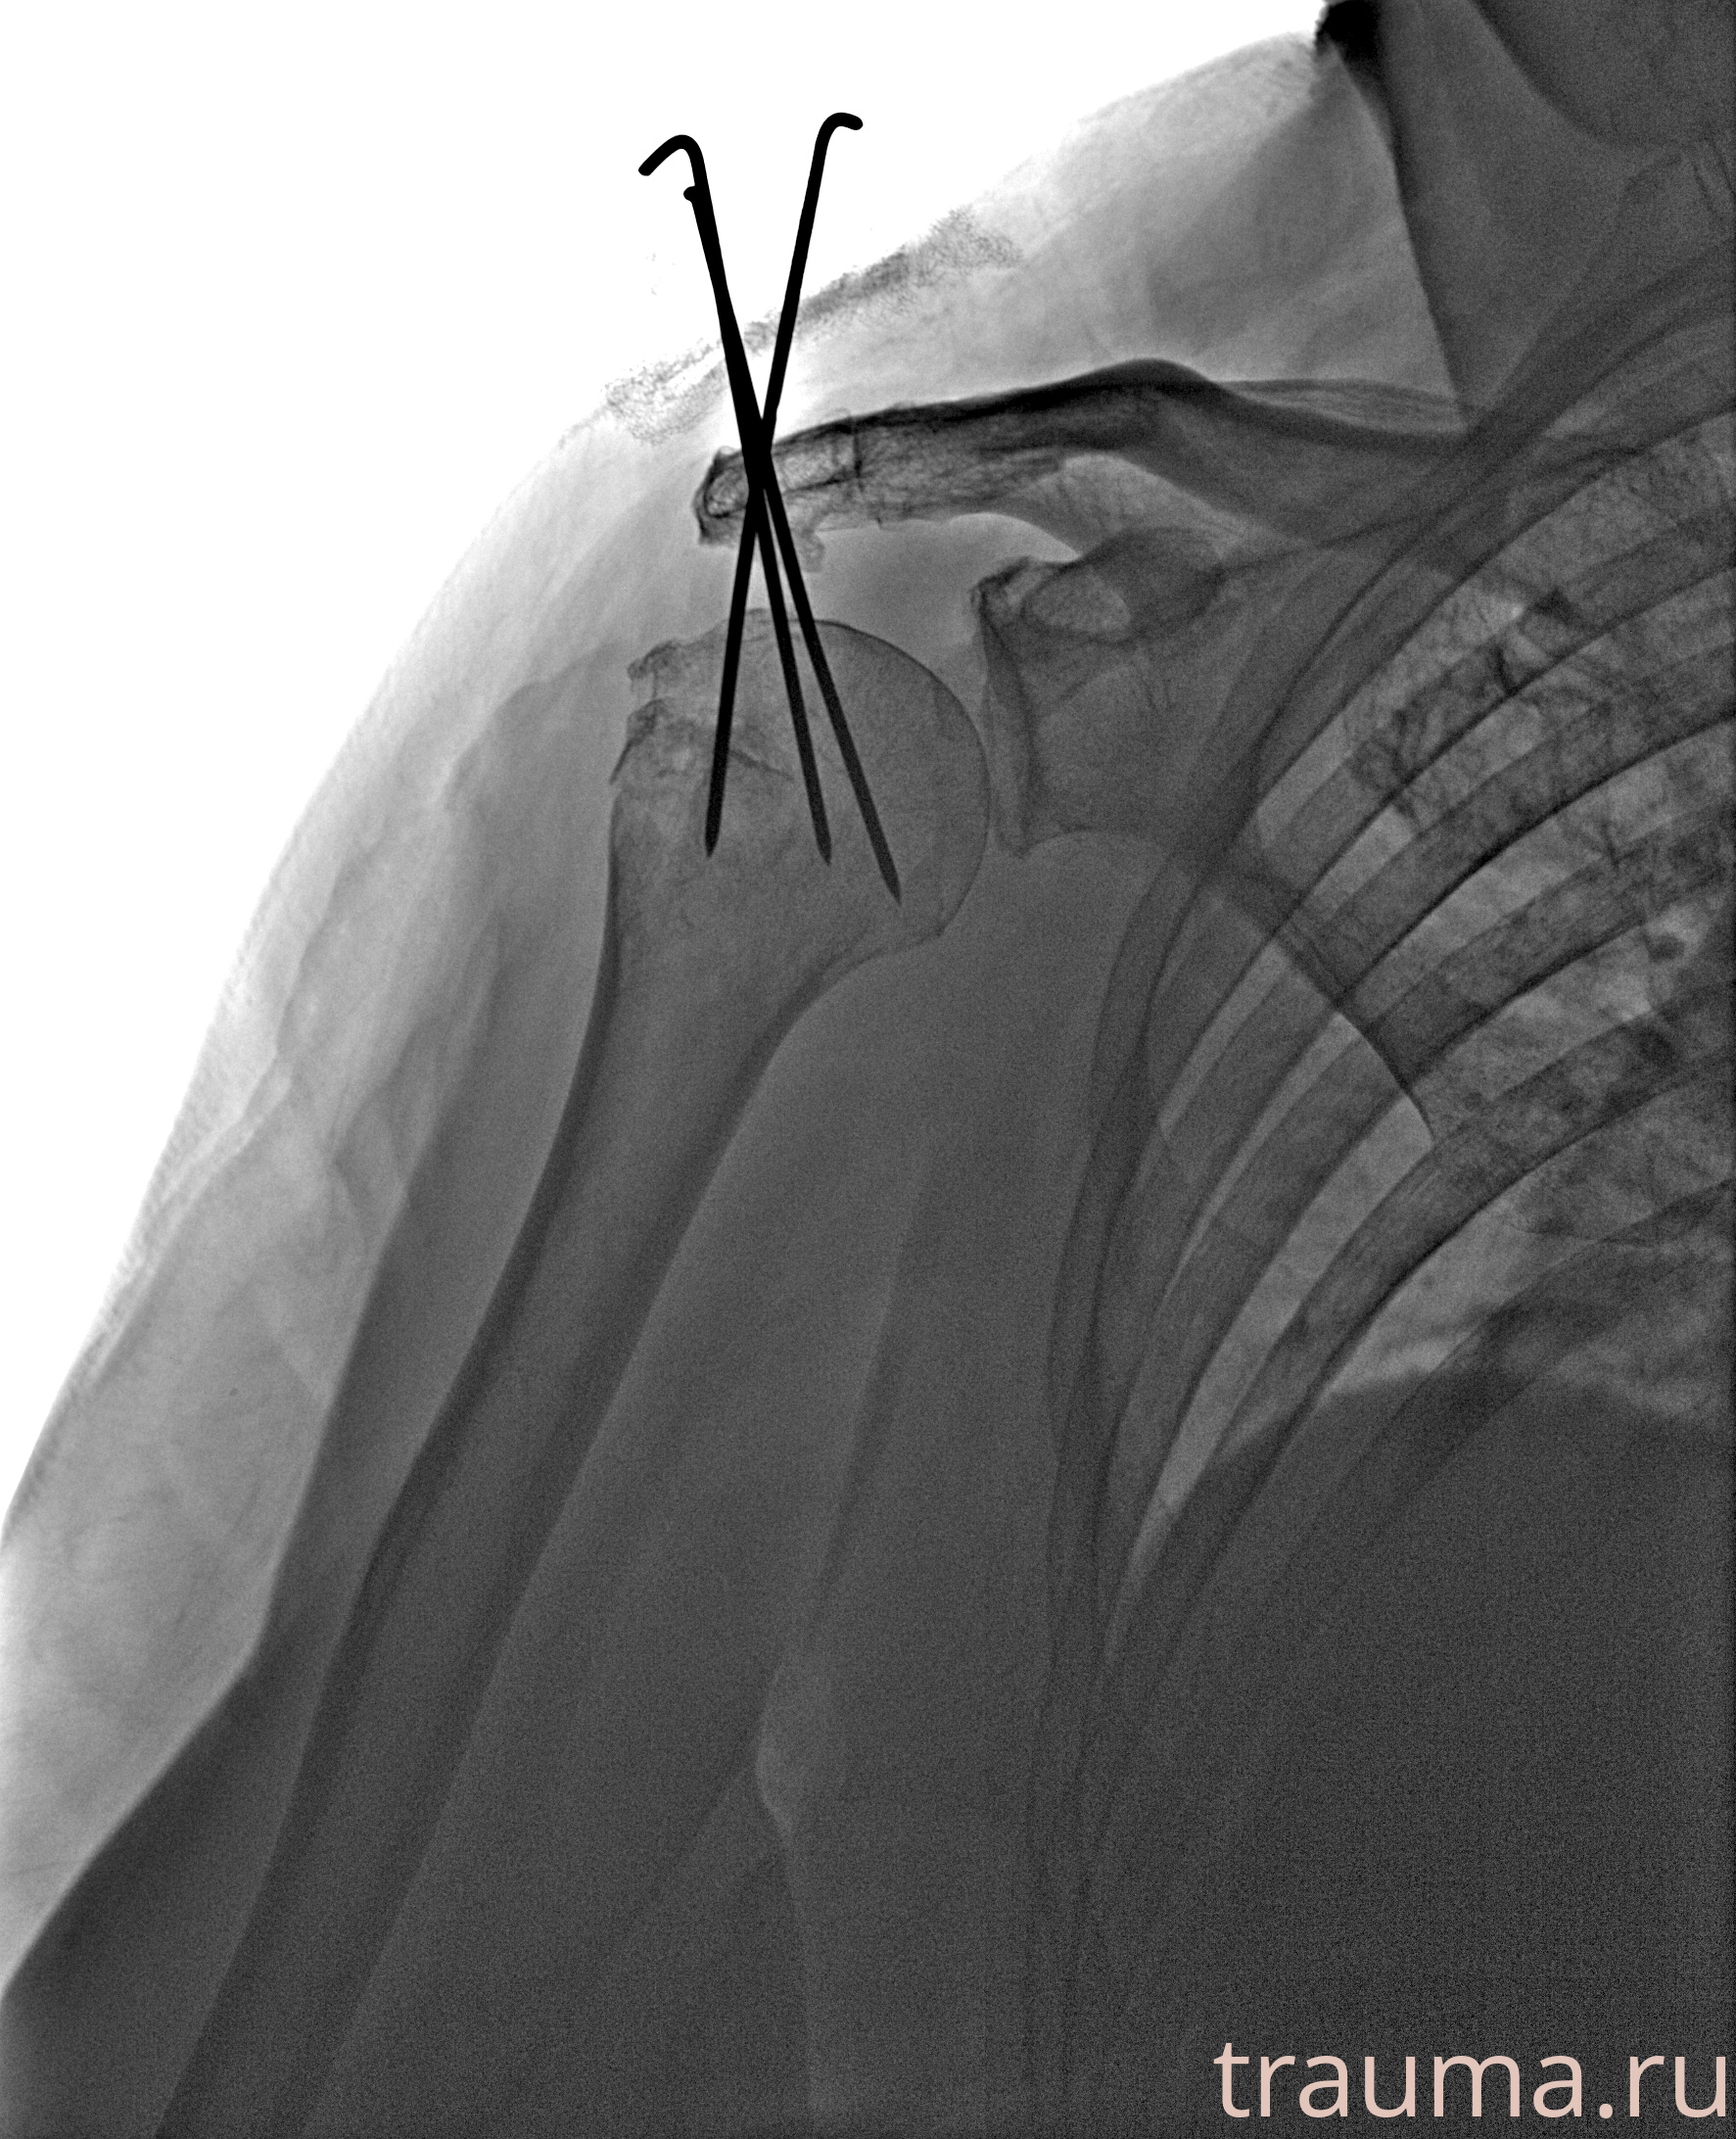

Рентгенограммы

Рентген на дому: по вашему адресу приезжает врач-рентгенолог, травматолог-ортопед с мобильным рентгеновским аппаратом, проводит диагностику травмы или заболевания, делает необходимые рентгенограммы, дает рекомендации по дальнейшему лечению. Получить качественные снимки в домашних условиях возможно благодаря уникальной методике, разработанной МосРентген Центром для института  Склифосовского